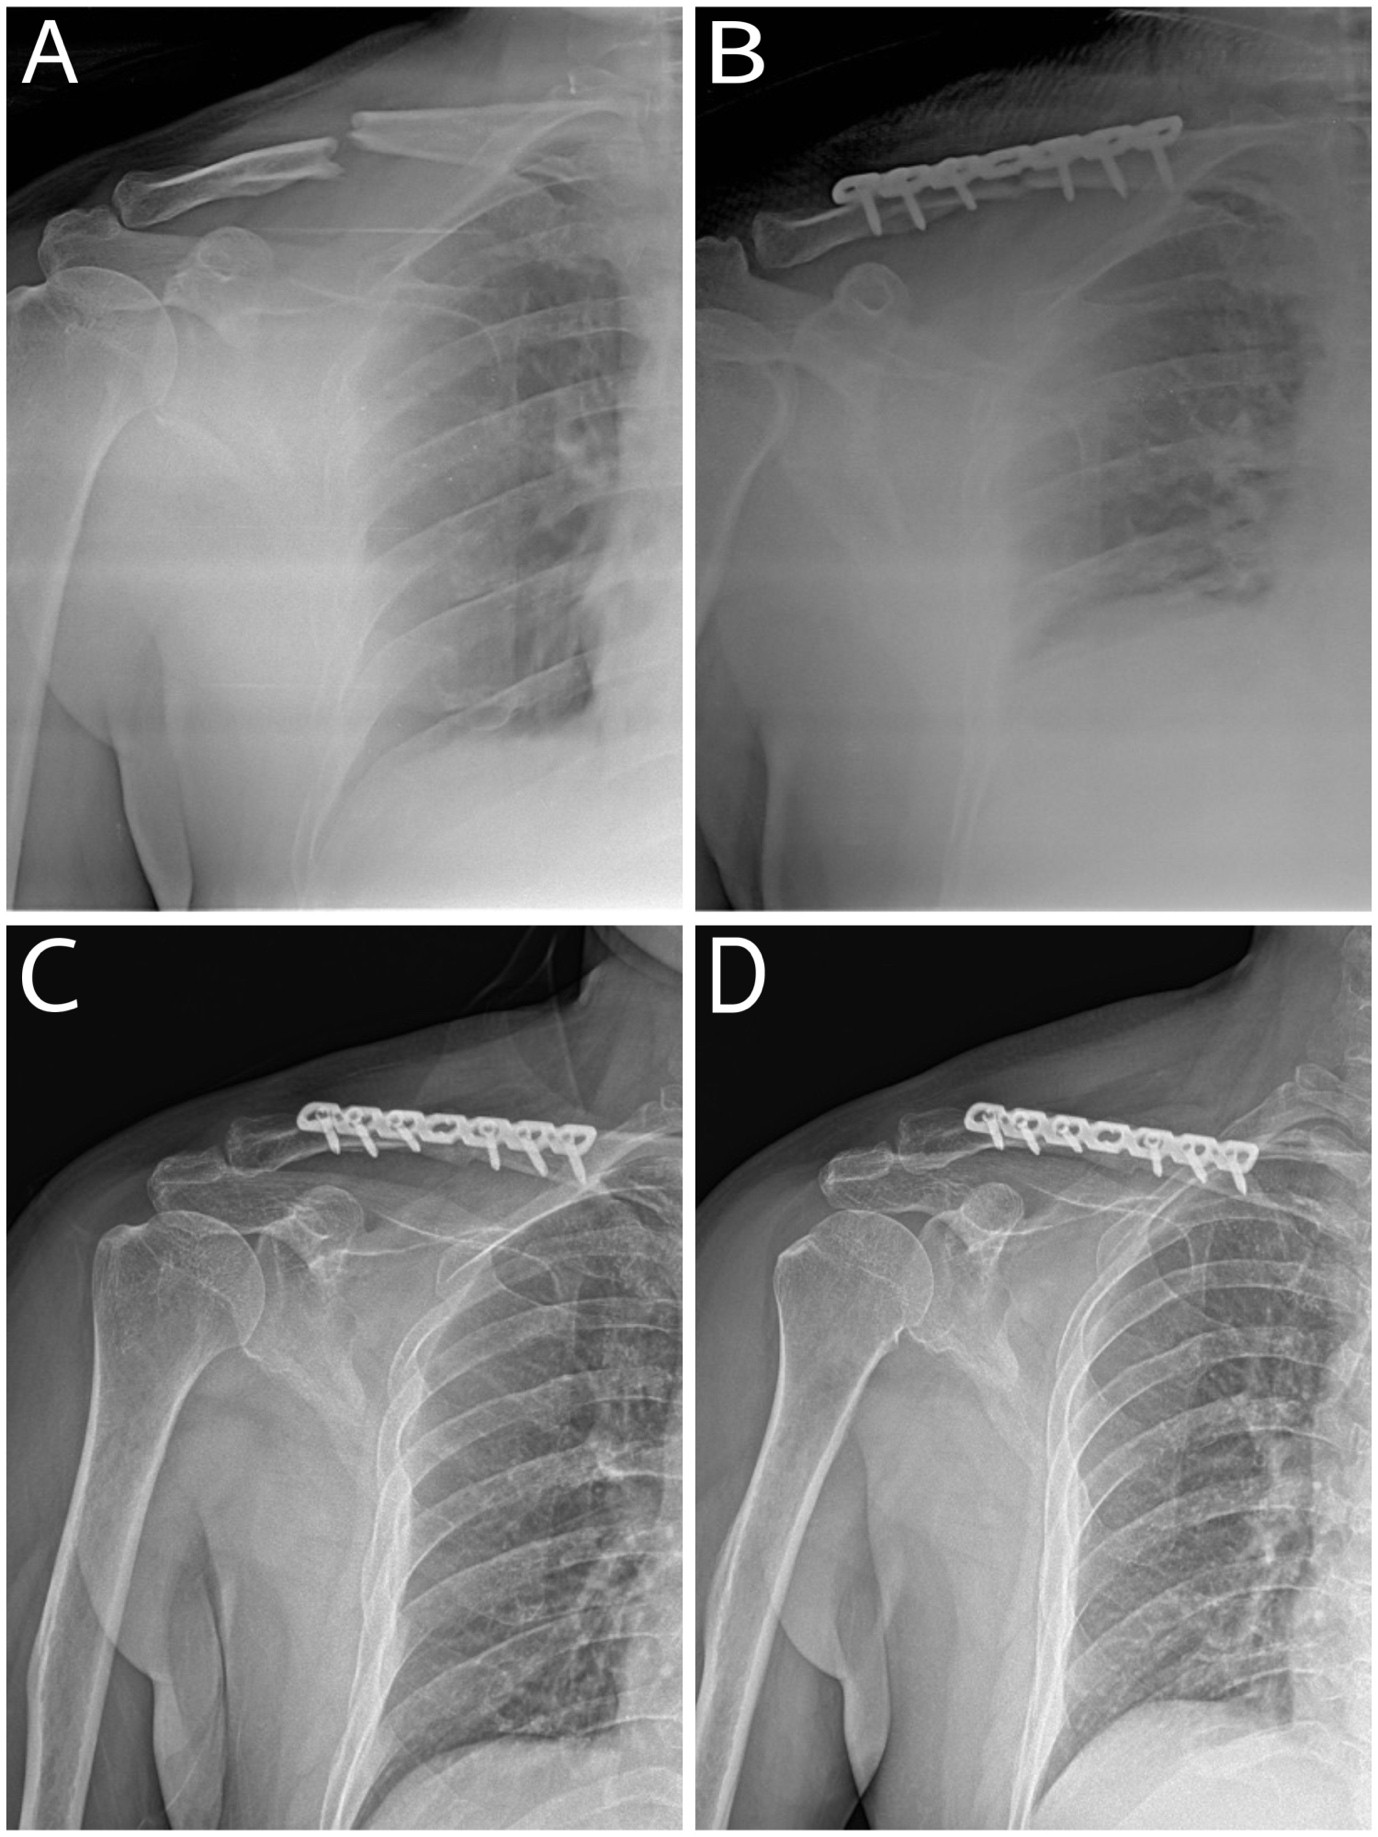

These findings indicate a progressive enhancement in shoulder function following anterior clavicle plating, with substantial recovery occurring within the first 6 months and further minor improvements up to 1 year post-surgery. Fig. 4 shows the sequential radiographs demonstrating the progression of fracture healing over time. The pre-operative X-ray (Fig. 4a) showed a midshaft clavicle fracture, while the immediate post-operative X-ray (Fig. 4b) confirmed proper fracture alignment and stabilization following anterior clavicle plating. The 1-year follow-up X-ray in Zanca view (Fig. 4c) revealed complete bone union and stable implant positioning, indicating successful healing and restoration of clavicular integrity.

Figure 4: X-rays showing the progression of fracture healing over time. *(a) Pre-operative X-ray, (b) Immediate post-operative X-ray, (c) 3 months follow-up (d) 6 months follow-up.